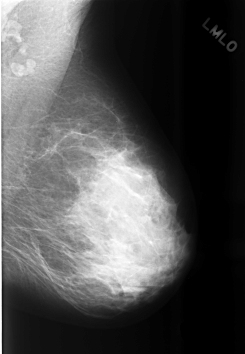

C_0478_1.LEFT_MLO

LEFT_MLO LINES 5656 PIXELS_PER_LINE 3920 BITS_PER_PIXEL 12 RESOLUTION 50 NON_OVERLAY